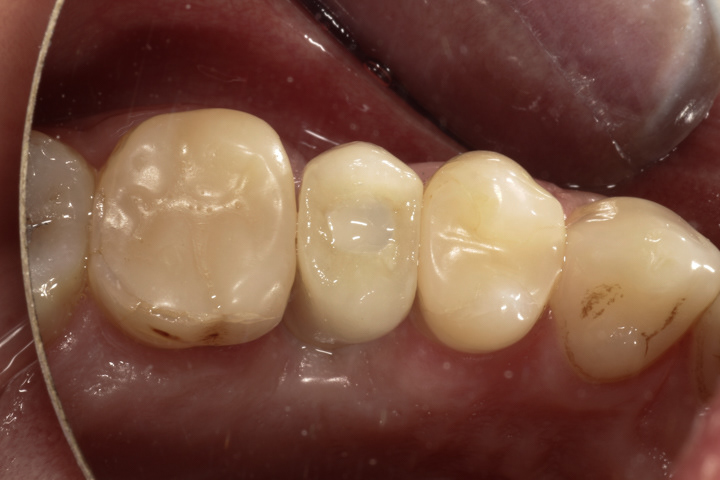

Alternatywą dla mostów są implanty, które pozwalają uzyskać całkowicie nowy ząb bez ingerencji w zęby sąsiednie. Mogą być zatem czyszczone nitką po obu stronach, lepiej prezentują się w strefach estetycznych. Ich wady to wyższa cena, dłuższy czas leczenia i wrażliwość na niedostateczną higienizację. Poniżej zamieszczam kilka przykładów wstawiania zębów za pomocą implantów.

Przykłady poniżej różnią się tym, że korona jest przykręcana a nie cementowana. Po dokręceniu korony otwór jest maskowany kompozytem. Z punktu widzenia trwałości takich uzupełnień jest to lepsza opcja od koron cementowanych, ponieważ trudne do oczyszczenia resztki cementu mogą prowadzić do zapalenia dziąsła na przestrzeni lat.